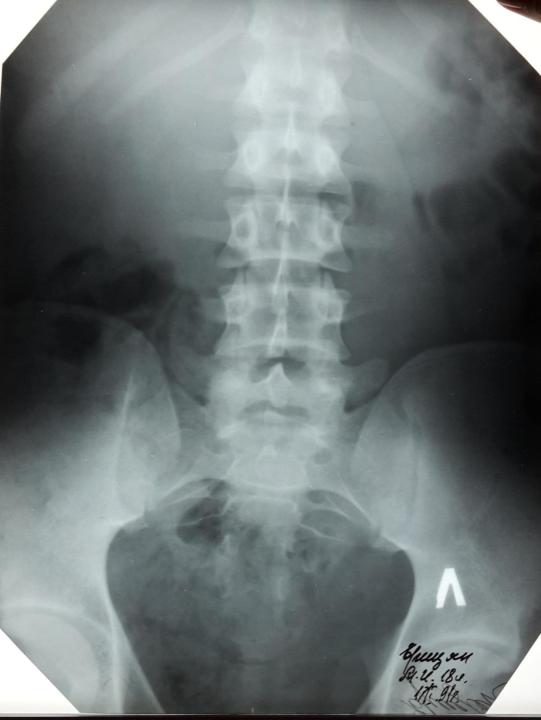

Болезнь Бехтерева

Анкилозирующий спондилартрит – заращение всех суставов позвоночника.

Обызвествление продольных связок делает такой позвоночник неподвижным.